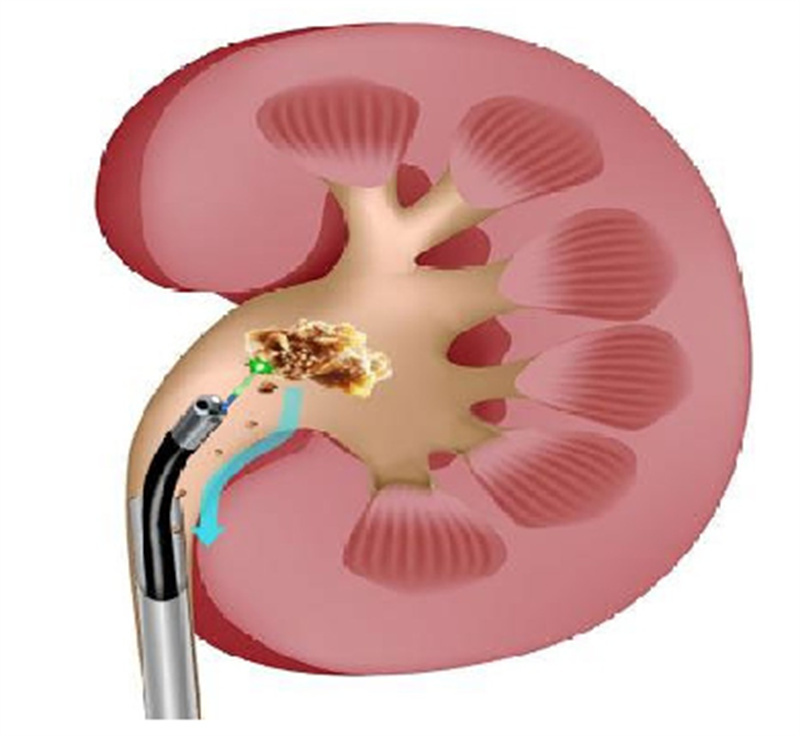

徐州市中医院泌尿外科郑典宝主任团队经过综合考虑和术前精心准备,为王女士实施在全麻下末端可弯曲负压吸引鞘输尿管软镜碎石取石手术,运用铥激光粉末化模式将结石击碎成粉末,利用负压吸引装置联合末端可弯曲负压吸引鞘将结石粉末吸出体外。

模式图

(负压吸引,边碎边吸,高效清石)

这一术式可做到术中视野清晰,持续肾内低压,降低脓毒血症概率,且术中即刻清除结石,结石残留率低,因此缩短患者术后留置双J管的时间,从而减轻了留置双J管引发的各种不适(血尿、腰痛等),由此保证了手术的安全性及高效碎石清石。